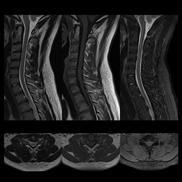

Lumbar Spine T1

Atlas SPEEDER Spine, AiCE + Compressed SPEEDER, Res: 0.35 x 0.35 mm, Scan time: 0:59 min.

Lumbar Spine T2

Atlas SPEEDER Spine, AiCE + Compressed SPEEDER, Res: 0.3 x 0.3 mm, Scan time: 0:57 min.

PD STIR - 1024 x 1024 matrix - 3mm slice thickness

Sag T2 - 0.5 x 0.5 min - 0:56 min Ax PD FatSat - 0.6 x 0.6 mm - 1:30 min Cor PD FatSat - 0.6 x 0.6 mm - 1:15 min Cor PD - 0.5 x 0.5 mm - 0:58 min © 2020 CANON MEDICAL SYSTEMS // MREU200040

Fast knee protocol with AiCE on Vantage Orian 1.5T